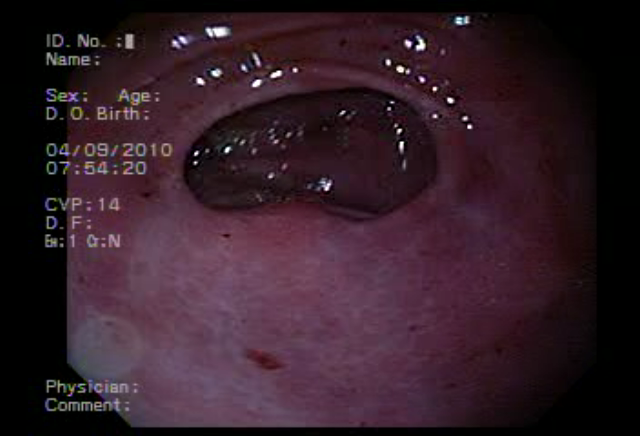

Cándida Esofagica |

Cáncer de Colon |

Gastropatia Severa |